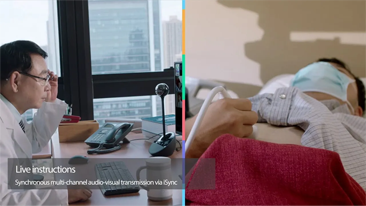

Desde su creaciÃģn, Mindray no ha dejado de explorar nuevas maneras de mejorar la fiabilidad del diagnÃģstico. Gracias a ZONE Sonography?, la tecnologÃa mÃĄs revolucionaria, la nueva plataforma ZST+ del Resona 7 eleva la calidad de imagen de ultrasonido mediante la adquisiciÃģn de zonas y el procesamiento de datos de canal.

AdemÃĄs de una calidad superior de la imagen, el Resona 7 tambiÃĐn mejora las capacidades de investigaciÃģn clÃnica gracias al revolucionario V Flow para la evaluaciÃģn hemodinÃĄmica vascular y la adquisiciÃģn de planos mÃĄs inteligente a partir de un conjunto de datos 3D para el diagnÃģstico CNS fetal. Combinando el funcionamiento multitÃĄctil mÃĄs intuitivo basado en gestos y todas las funciones clÃnicas esenciales, el Resona 7 estÃĄ realmente encabezando nuevas ondas en la innovaciÃģn del campo del ultrasonido.